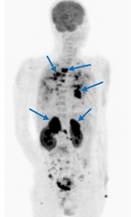

Ca lâm sàng 3: Bệnh nhân Nguyễn X.T., nam, 58 tuổi. Chẩn đoán: U lympho ác tính không Hodgkin, GPB: WF6. Hình PET cho thấy tổn thương ở phổi, hạch, xương, tuyến thượng thận hai bên (mũi tên). Hình CT và PET/CT cho thấy tổn thương tăng hấp thu FDG tại vị trí tuyến thượng thận hai bên (mũi tên).

Ca lâm sàng 4: Bệnh nhân Lê V.T., nam, 73 tuổi. Chẩn đoán: U lympho ác tính không Hodgkin biểu hiện ở màng cứng ống tủy sống. Hình PET/CT cho thấy tổn thương tăng hấp thu FDG tại ống tuỷ sống